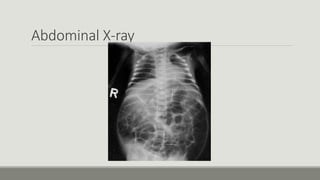

Abdominal X-ray

Abdominal plain X-rays